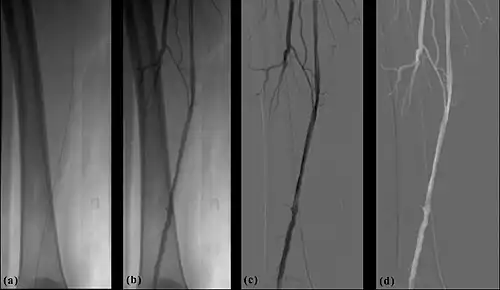

- The temporal-averaging feature of digital noise reduction can also be used for image presentation purposes so that the time course of the movement of contrast medium during a study can be displayed using just one image - see an example in Figure 7.4 from the peripheral study shown above - instead of a sequence of numerous images. Such an image is sometimes referred to as a Vascular Trace.

- One method of temporal filtration, referred to as Integrated Mask-Mode DSA involves adding (also called integrating) a number of images, acquired prior to the arrival of the contrast medium, to form an integrated mask image and adding a number of peak-opacification images to form an integrated live image. This is the process that was used to generate the vascular trace image in Figure 7.4. Thus, when four images are used to generate each integrated mask and live images, eight of the 25 images are now used in the subtraction process and, as a result, only 68% of the dose is wasted, and a subtraction image with lower noise results.